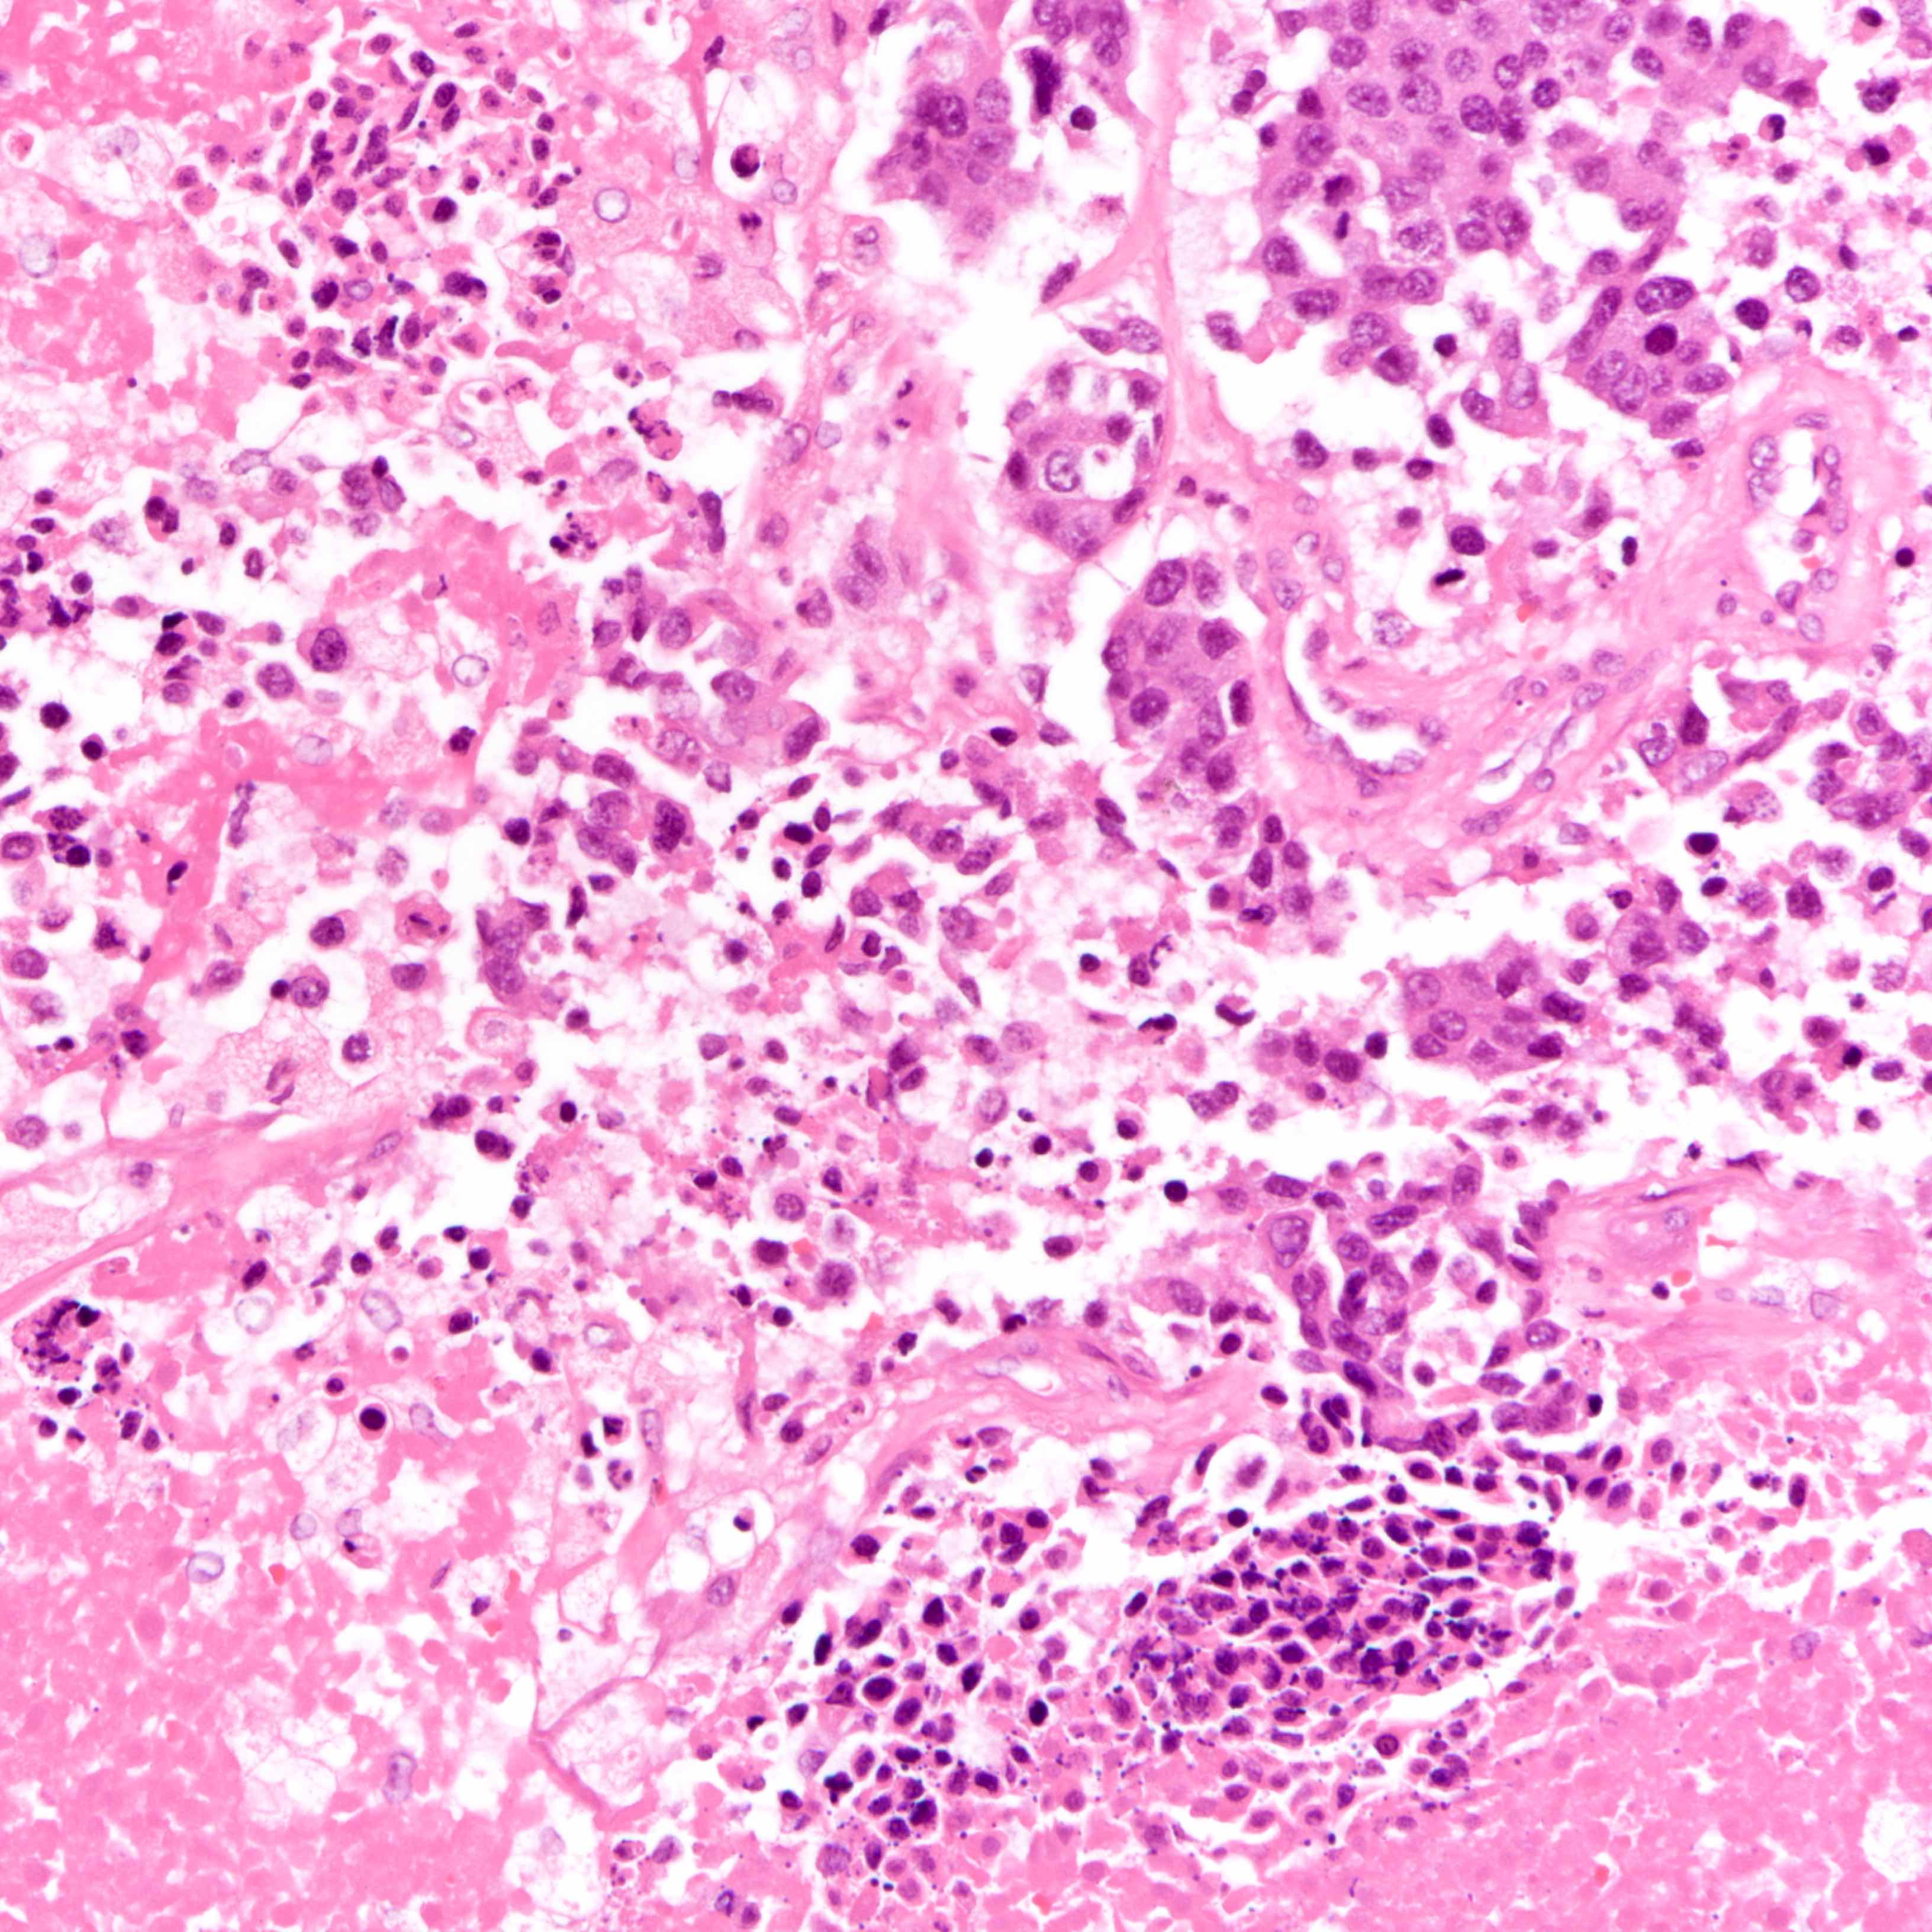

Microscopic (histologic) description

- Histologic evidence of tumor response includes fibrosis, hyalinization, lymphohistiocytic infiltration, hemosiderin laden macrophages, giant cell formation and vascular proliferation

- These histologic features are indicative of the tumor bed

- Patterns observed in partial response includes concentric tumor shrinkage, reduction in tumor cellularity and scattered multifocal tumor deposits (Mod Pathol 2015;28:1185)

- Tumor cells show degenerative changes including nuclear and cytoplasmic vacuolation, karyorrhexis, karyolysis and pyknosis (Int J Appl Basic Med Res 2012;2:111)

- There may be a change in histologic grading after neoadjuvant therapy

Microscopic (histologic) images

Contributed by Joshua J.X. Li, M.B.Ch.B., Gary M. Tse, M.B.B.S. and Emily S. Reisenbichler, M.D.